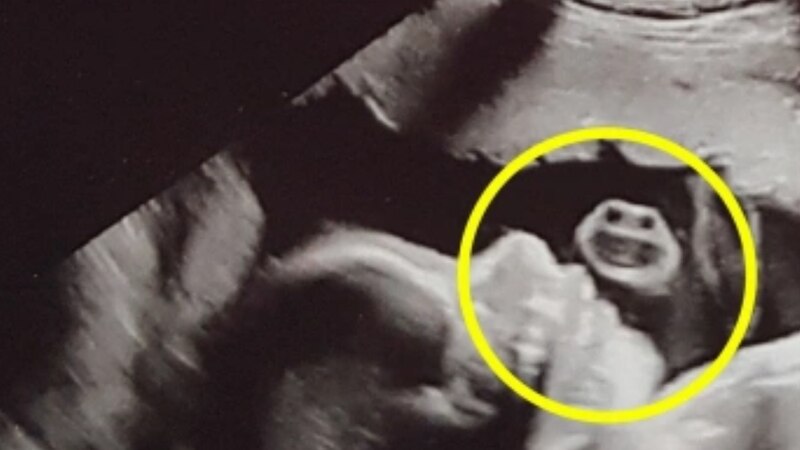

Sin embargo, cuando giró la cabeza y vio lo que el monitor reflejaba, se asustó por una curiosa imagen que aparecía allí: si, parecía un pequeño “monstruo”.

Claro está que no estaba refiriéndose a su pequeño hijo, sino a la forma de una “cara” que aparecía alrededor del bebé.

Todavía sorprendida por la curiosa imagen, la joven decidió compartir la foto con el resto de sus contactos y también en las redes sociales.

“Puse una actualización de mi estado y la gente empezó a comentar. No me había dado cuenta de lo que se había proyectado”, indicó la mujer oriunda de Inglaterra.